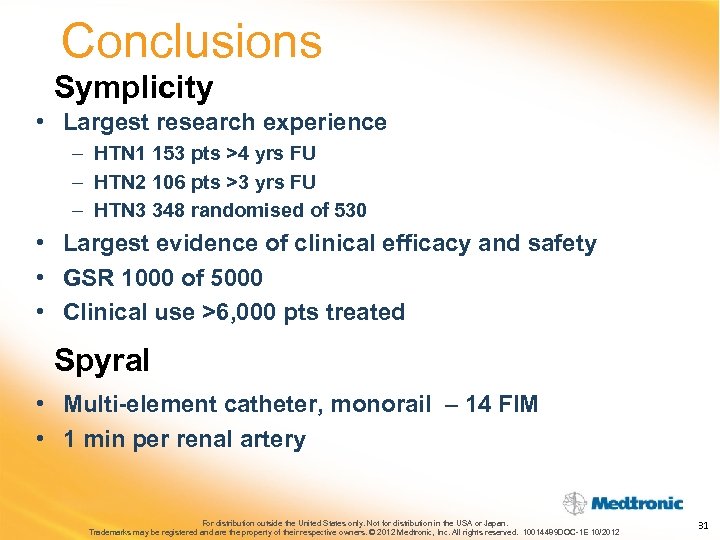

Conclusions Symplicity • Largest research experience – HTN 1 153 pts >4 yrs FU – HTN 2 106 pts >3 yrs FU – HTN 3 348 randomised of 530 • Largest evidence of clinical efficacy and safety • GSR 1000 of 5000 • Clinical use >6, 000 pts treated Spyral • Multi-element catheter, monorail – 14 FIM • 1 min per renal artery For distribution outside the United States only. Not for distribution in the USA or Japan. Trademarks may be registered and are the property of their respective owners. © 2012 Medtronic, Inc. All rights reserved. 10014489 DOC-1 E 10/2012 31

Conclusions Symplicity • Largest research experience – HTN 1 153 pts >4 yrs FU – HTN 2 106 pts >3 yrs FU – HTN 3 348 randomised of 530 • Largest evidence of clinical efficacy and safety • GSR 1000 of 5000 • Clinical use >6, 000 pts treated Spyral • Multi-element catheter, monorail – 14 FIM • 1 min per renal artery For distribution outside the United States only. Not for distribution in the USA or Japan. Trademarks may be registered and are the property of their respective owners. © 2012 Medtronic, Inc. All rights reserved. 10014489 DOC-1 E 10/2012 31